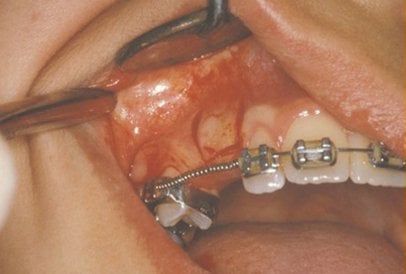

In cases where the eyeteeth will not erupt spontaneously, the orthodontist and oral surgeon will work together to get these teeth to erupt. Each case must be evaluated on an individual basis, but treatment will usually involve a combined effort between the orthodontist and the oral surgeon. The oral surgeon will expose and bracket the impacted eyetooth.

The goal is to erupt the impacted tooth and not to extract it. Once the tooth has moved into its final position, the gum around it will be evaluated. In some circumstances, there may be some minor “gum surgery” required.

Exposure and Bracketing of an Impacted Cuspid

What to expect from surgery to expose & bracket an impacted tooth

The surgery to expose and bracket an impacted tooth is a very straightforward surgical procedure that is performed in the oral surgeon’s office. For most patients, it is performed using laughing gas and local anesthesia. In selected cases it will be performed under IV sedation if the patient desires to be asleep, but this is generally not necessary for this procedure. If the procedure only requires exposing the tooth with no bracketing, the time required will be shortened by about one half. These issues will be discussed in detail at your preoperative consultation with your doctor.